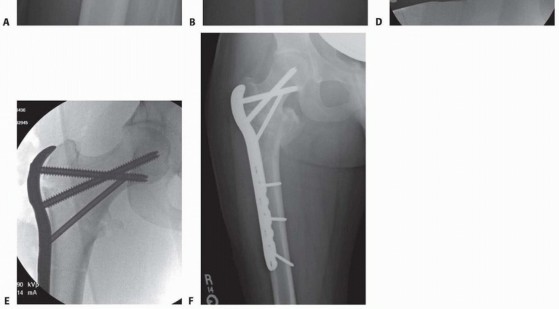

### TECH FIG 1 • Fracture reduction. A. Preoperative peritrochanteric fracture. B. Position of the fracture after longitudinal traction. C. Position of the fracture after longitudinal traction and abduction applied. D. Position of the fracture after longitudinal traction, abduction, and internal rotation applied. E. Posterior fracture sag. F. Position of the fracture after longitudinal traction, abduction, internal rotation, and flexion force applied with a crutch under the leg. G. Intraoperative picture of crutch placed under distal fragment. Fracture reduction is next checked in the lateral plane. The distal femur tends to sag posteriorly while the proximal fragment is flexed by the iliopsoas. This can be corrected by placing a crutch under the femoral shaft for support. Alternatively, some fracture tables have padded attachments to support the thigh. Fracture reduction is reassessed in both the AP and lateral planes and checked for neck-shaft angle, neck anteversion, rotation, and femoral shaft sag, with a goal of obtaining a near-anatomic reduction. Acceptable parameters include normal or slight valgus reduction, less than 20 degrees of angulation on the lateral radiograph, and less than 4 mm of fracture translation. 1 If a near-anatomic closed reduction cannot be obtained, percutaneous techniques can include use of Schanz pins, a bone hook, or an elevator used to manipulate fracture fragments. In the event that reduction is still inadequate, open reduction is necessary. 407 1. ## Side Plate and Sliding Hip Screw ### Approach Because of the muscular forces exerted on the fracture fragments associated with peritrochanteric hip fractures, anatomic reduction of the fracture is close to impossible with indirect methods, especially in the coronal plane, which is often the most difficult plane to control.** Studies have shown that absolute anatomic reduction of all fragments of these fractures is not necessary for a satisfactory functional outcome. 14 The primary goal of reduction of peritrochanteric hip fractures is to reestablish a normal anatomic alignment between the proximal head and neck fragment and the distal femoral shaft in the coronal, sagittal, and axial planes. A lateral approach to the proximal femur is the preferred approach for open reduction and internal fixation of peritrochanteric femur fractures. This approach may be used whether the selected implant is a side plate, a blade plate, or a proximal femoral locking plate. The incision is centered over the lateral aspect of the femur. Its proximal extent is the palpable vastus ridge for sliding hip screw devices and just proximal to the tip of the greater trochanter for fixed-angle plates. The distal extent of the incision is made long enough to allow application of the plate.

### TECH FIG 3 • Implant insertion. A. Lag screw and side plate on inserter. B. Placement of side plate. C. Implant in place. D. Traction released. E. Fracture after compression. A triple reamer is used to prepare the channel in the lateral cortex, neck, and head for the lag screw and side plate barrel. The reamer is set to 5 mm less than the measured lag screw length to ensure that the subchondral bone in the femoral head is not violated during reaming. The triple reamer is then advanced and withdrawn under fluoroscopic guidance. It is important to use fluoroscopy during reaming to ensure that the guide pin is not bonded to the reamer and inadvertently advanced into the pelvis. The channel is reamed to its proper length and removed under fluoroscopic guidance, ensuring that the guide pin is not withdrawn with the reamer. An obturator may be used to help prevent the pin from backing out. Occasionally, the intact lateral wall of the proximal femur may be fractured by the triple reamer. If this occurs, the fracture is essentially converted into a transverse or reverse oblique pattern (AO/OTA type 31-A3), and excessive fracture collapse will occur if fixed only with a sliding hip screw. In these cases, the proximal lateral wall may be buttressed with the addition of a trochanteric stabilizing plate in conjunction with a sliding hip screw. Alternatively, the decision may be made to convert to an intramedullary device for fracture fixation. ### Implant Insertion A two- to four-hole side plate is usually chosen for fixation ( TECH FIG 3). Multiple clinical and cadaveric studies have shown no difference in the strength of implant fixation with side plates with more than four holes. 3, 10 The implant is set up according to the manufacturer's specifications. The cannulated lag screw is then inserted over the guide pin with a centering sleeve to ensure proper positioning. Careful sizing of the lag screw length is required, as noted earlier, to ensure that fracture compression does not lead to excessive screw length and lateral hardware prominence. 409 Fluoroscopy and manual fracture palpation are used to ensure that the fracture is not displaced (rotated) while the lag screw is inserted. If the fracture is displaced by the insertion of the lag screw, it is removed, a derotation screw is added, the channel is tapped, and the lag screw is reinserted. Peritrochanteric fractures of the right hip tend to displace to an apex posterior angulation as the lag screw is turned clockwise during insertion, whereas left hip fractures tend to displace to an apex anterior angulation owing to the anatomic configuration and subsequent tensioning of the hip capsule with screw insertion. With the lag screw inserted to the desired depth within the femoral head on the AP and lateral fluoroscopic projection, its relation to the lateral cortex is checked to ensure proper length. Ideal position of the distal tip of the screw is approximately 5 to 8 mm deep to the lateral cortex. The side plate is then slid over the lag screw and inserter so it is seated on the lateral cortex, and the guide pin (and derotational pin if used) is removed. Traction is released at this point to allow slight impaction of the fracture in the axial plane. Cortical screws are inserted to secure the plate to the femoral shaft. If appropriate for the fracture pattern, the lag screw compressing screw is then inserted into the barrel of the lag screw and tightened to compress the fracture in the plane of the lag screw, under fluoroscopic guidance. The compression screw may be removed in certain cases. If the fracture is oriented such that weight bearing will cause compression at the fracture site, it is reasonable to remove the compression screw. It is mandatory to use and retain the compressing screw in paralytics, where there is no resting joint reaction force, and implant disengagement can occur with postoperative transfers. With the compression of the fracture complete, the alignment and implant position are checked once again with fluoroscopy. 1. ## Blade Plate ### Approach A lateral approach is used, as described earlier. Although the incision is more proximal, and angles toward the anterior superior iliac spine, the trochanteric block must be exposed and interval between tensor and gluteus medius must be exploited in order to visualize anterior neck. ### Preparation and Implant Insertion With the lateral femur and trochanteric block exposed, if a direct reduction is desired, a soft tissue-sparing reduction of the trochanteric block to the proximal femur is secured with pointed bone clamps and K-wires or small lag screws ( TECH FIG 4). Alternatively, an indirect reduction can be employed, relying on the proper position of the blade within the proximal segment to reduce the fracture when the plate is brought onto the shaft. Guide pins are then introduced into this reconstructed segment to facilitate proper seating of the chisel for the blade plate. The first pin is placed anterior to the femoral neck and secured into the anterior femoral head to demonstrate the femoral anteversion. The second pin is placed with the use of an angled guide and/or fluoroscopy near the tip of the greater trochanter and directed into the femoral head at a 90-degree angle to the femoral shaft. The chisel is inserted parallel to the two guide pins, just distal to the second pin. Care must be taken to maintain the correct alignment of the chisel with the shaft of the femur because this determines the flexion-extension of the fracture, which is fixed once the blade plate is inserted. The chisel is directed so as to pass through the center of the neck and seat in the inferior portion of the femoral head. Because of the anterior translation of the femoral head on the shaft, the insertion site is in the anterior half of the trochanter. The position of the chisel should be constantly checked with fluoroscopy before and during its insertion. The chisel is carefully removed and the appropriate-length blade plate is inserted and gently seated into the proximal fragment. The insertion should be frequently checked with biplanar fluoroscopy to ensure that the blade follows the path made by the chisel. Once the blade is seated, the most proximal screw is placed through the implant into the medial cortex of the proximal femoral neck, rigidly securing the implant to the proximal fragment. Fracture reduction is now achieved by bringing the plate to the shaft and controlling length and rotation. If needed, a femoral distractor may be used as a reduction tool. The distractor should be fixed to the lateral aspect of the femur, with the proximal pin in the head and neck fragment and the distal pin placed distal to the end of the plate. Distraction is applied across the fracture to improve fracture alignment and length through soft tissue tensioning. A bone clamp is loosely applied to the distal femoral shaft fragment and plate to counteract the tendency for the fracture to be reduced into varus with the femoral distractor. Pointed reduction clamps are used to reduce comminuted fragments to the plate without stripping them of soft tissue attachments. Fracture reduction is checked with fluoroscopy. If fracture alignment is acceptable, the distraction is taken off to allow fragment settling and fracture compression. The plate is then fixed to the shaft fragments with screws in the standard manner, and lag screws are inserted where the pointed reduction clamps were previously placed. The final fracture alignment and length, as well as the femoral head, are examined with fluoroscopy to ensure proper fracture reduction and to make sure that there has been no head penetration by the implant. 410

### TECH FIG 4 • Blade plate insertion. A,B. Preoperative AP and lateral radiographs of a type 31-A3 fracture in a 28-year-old man. C. Chisel inserted after femoral head and neck and trochanteric block were secured with lag screws. D. Insertion of blade plate. E. Postoperative AP radiograph. -